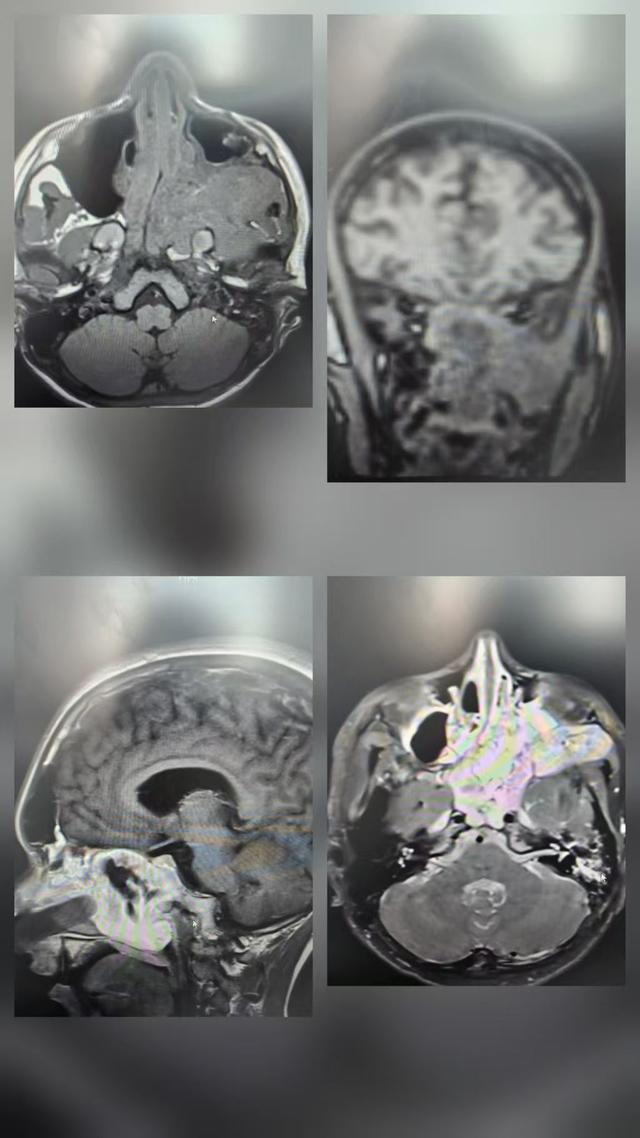

新年第三天,莎车县人民医院耳鼻喉颌面外科主任朱学武接诊了一名15岁男性患者。该患者持续鼻出血4天,已陷入失血性休克,情况危急。结合鼻内镜检查与临床经验,朱学武主任迅速判断其为高风险鼻颅底血管瘤。

朱学武主任立即实施前鼻孔填塞止血,开具住院证并通过绿色通道紧急收治。患者入院后,主管医生快速完善检查,确诊为“鼻颅底血管瘤伴失血性休克”。

医疗团队第一时间联系上海援疆介入专家童进东主任。童主任阅片后,考虑病变累及颅底、风险极高,建议由上海援疆医疗队队长刘超博副院长亲自主刀栓塞。

医院随即组织高规格多学科诊疗(MDT)讨论,由新疆医科大学第一附属医院援莎医疗队队长白磊院长主持,刘超博副院长领衔,多学科主任共同研判,最终确定“两步走”方案:

第一步:由刘超博副院长主刀,实施介入动脉栓塞术,堵塞肿瘤供血血管;

第二步:由朱学武主任、王松主任联合主刀,开展鼻颅底血管瘤切除手术。